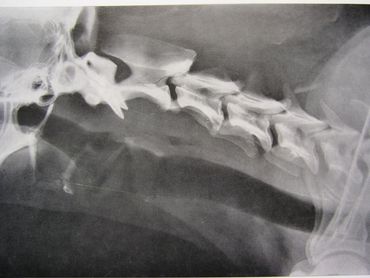

The spinal column is made up of four major vertebral regions: cervical (neck), thoracic (mid back), lumbar (low back) and sacral (pelvic). Dogs have seven cervical, thirteen thoracic, seven lumbar and three sacral vertebrae. There are also variable numbers of coccygeal or tail vertebrae. Intervertebral disks are located between the vertebral bodies starting at the second and third cervical vertebrae (C2-3) and extending to the seventh lumbar and first sacral vertebrae (L7-S1). The three sacral vertebrae are fused and therefore do not have disks. Intervertebral disks are present between the coccygeal vertebra as well, but are of little clinical significance.

The canine spinal anatomy is very similar to us humans, with the exception of 1 additional thoracic vertebra and 2 additional lumbar vertebra...